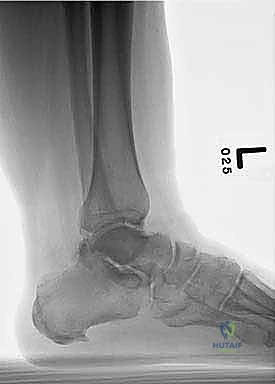

تاريخياً، تم استخدام المسامير النخاعية (Intramedullary Nails) أو البراغي العادية لدمج الكاحل. ولكن في الحالات شديدة التعقيد، حيث تكون عظمة الكاحل (Talus) مدمرة تماماً ويجب استئصالها (Talectomy)، تصبح المسألة هي كيفية تثبيت قصبة الساق مباشرة بعظمة الكعب (Tibiocalcaneal Fusion).

هنا تبرز الصفيحة النصلية (Blade Plate) كالحل الذهبي. تتميز هذه الصفيحة بوجود "نصل" صلب يتم إدخاله بقوة داخل عظمة الكعب، بينما يتم تثبيت الجزء الطولي من الصفيحة على عظمة قصبة الساق بالبراغي. هذا التصميم الهندسي يوفر مقاومة هائلة لقوى الانحناء والدوران، مما يضمن ثباتاً فورياً يسمح للعظام بالالتحام بشكل مثالي.

يبدأ الإجراء بتخدير المريض وتجهيز الطرف المصاب في بيئة معقمة تماماً. يتم استخدام جهاز الأشعة السينية المرئي (C-arm) لضمان الدقة المطلقة في كل خطوة.